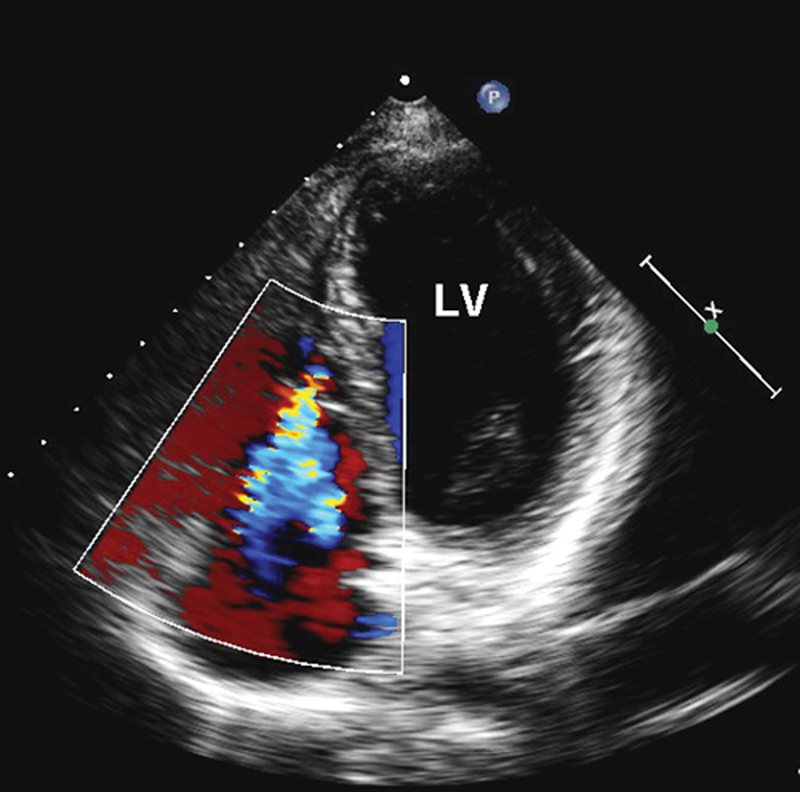

فحوصات تشخيصية لبعض امراض القلب والشرايين التاجية